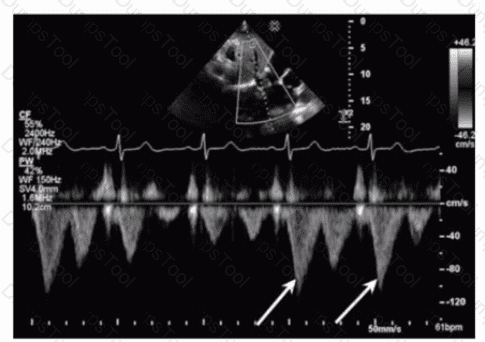

The sonographer obtains this Doppler signal while using the non-imaging transducer in the apical position. What is the best way to differentiate between mitral regurgitation and aortic stenosis signals in the waveform shown in this image?